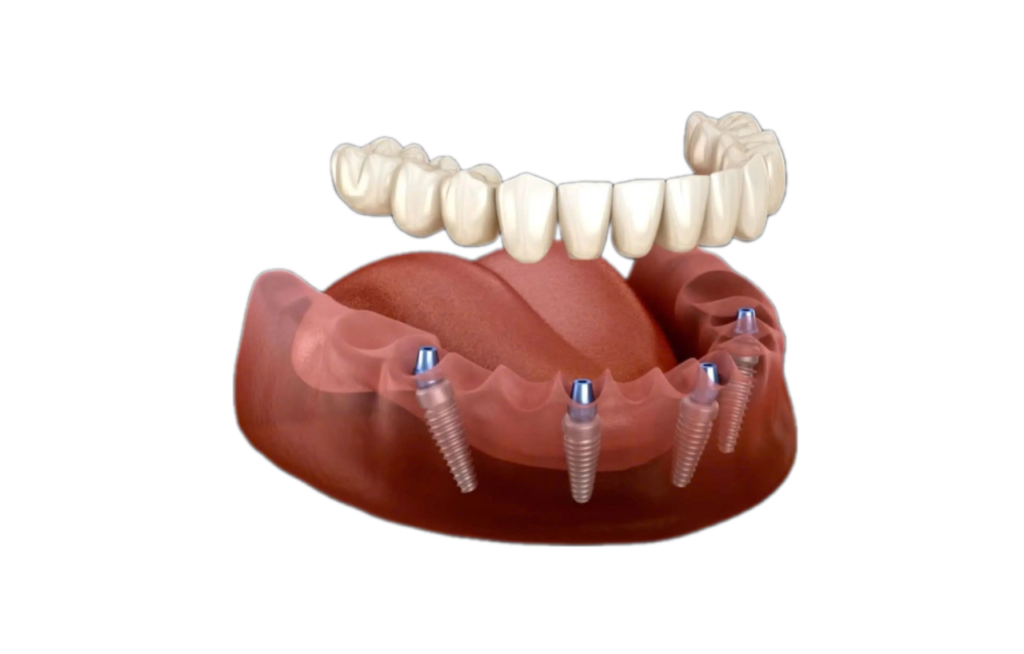

Trồng răng Implant 1 răng là phương pháp phục hồi răng mất tiên tiến, sử dụng trụ chụ chân răng nhân tạo – Implant từ titanium cấy vào xương hàm để thay thế chân răng đã mất. Sau đó, một mão răng sứ được gắn lên trụ, tạo ra chiếc răng mới với hình dáng và chức năng giống như răng thật.